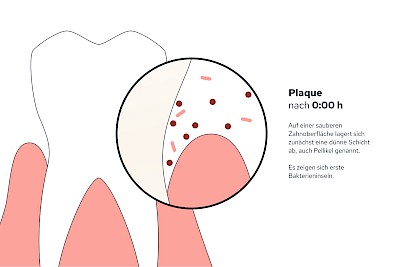

Plaque (Biofilm)

Als Plaque bzw. Biofilm bezeichnet man die Gesamtheit aller Mikroorganismen (Mikrobiom) auf der Zahnoberfläche. Werden die Zähne nicht geputzt, haften die Beläge nach 24 Stunden bereits so fest, dass diese mit der Zahnbürste schon nicht mehr vollständig entfernt werden können.